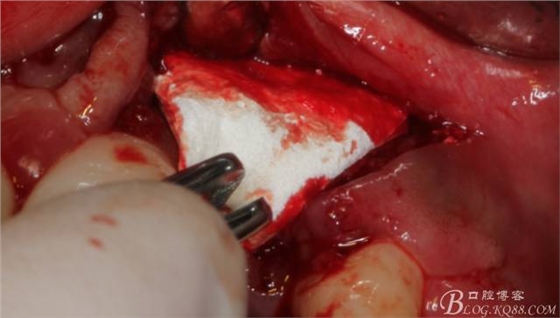

將自體骨與BIO-OOS骨粉混合植到術(shù)區(qū),蓋生物膜。

縫合。